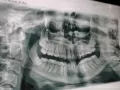

• Определить необходимость хирургического вмешательства можно только на основании клинического осмотра и диагностических мероприятий. Вам необходимо сделать рентгеновские снимки, которые называются ортопантомограмма и телерентгенограмма и обратиться к стоматологу-ортодонту.